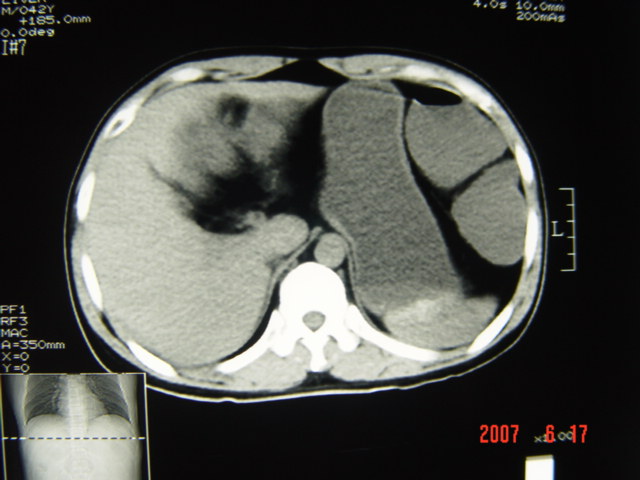

[br][br]以下是引用lkc8963在2007-6-17 13:32:00的发言:[br]完全支持邓主任意见:降/乙交界部占位性病变伴不全梗阻.做个增强或者be可能更好.